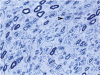

Recessive Charcot-Marie-Tooth disease type-4J (CMT4J) and its animal model, the pale tremor mouse (plt), are caused by mutations of the FIG4 gene encoding a PI(3,5)P(2) 5-phosphatase. We describe the 9-year clinical course of CMT4J, including asymmetric, rapidly progressive paralysis, in two siblings. Sensory symptoms were absent despite reduced numbers of sensory axons. Thus, the phenotypic presentation of CMT4J clinically resembles motor neuron disease. Time-lapse imaging of fibroblasts from CMT4J patients demonstrates impaired trafficking of intracellular organelles because of obstruction by vacuoles. Further characterization of plt mice identified axonal degeneration in motor and sensory neurons, limited segmental demyelination, lack of TUNEL staining and lack of accumulation of ubiquitinated protein in vacuoles of motor and sensory neurons. This study represents the first documentation of the natural history of CMT4J. Physical obstruction of organelle trafficking by vacuoles is a potential novel cellular mechanism of neurodegeneration.